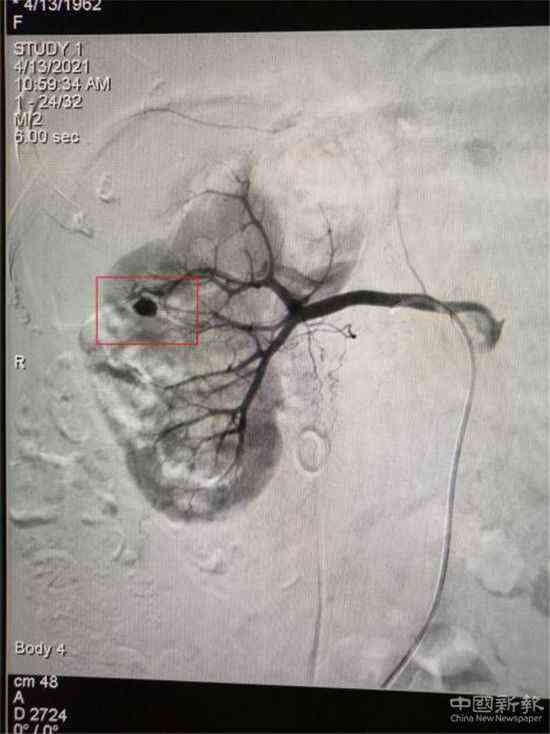

栓塞前造影圖(紅圈標記為出血處)

家住湖南省郴州市嘉禾縣廣發(fā)鎮(zhèn)的鄧大媽,因患巨大腎結石進行了“經皮腎鏡取石術”,術后第3天出現(xiàn)大量鮮紅色血尿。經過增強CT檢查,考慮為“腎穿刺口處動脈出血”,醫(yī)院介入血管外科團隊立即為患者在DSA下行“微創(chuàng)介入右腎出血動脈栓塞術”,術后出血立刻停止,尿液由紅色轉為正常顏色。